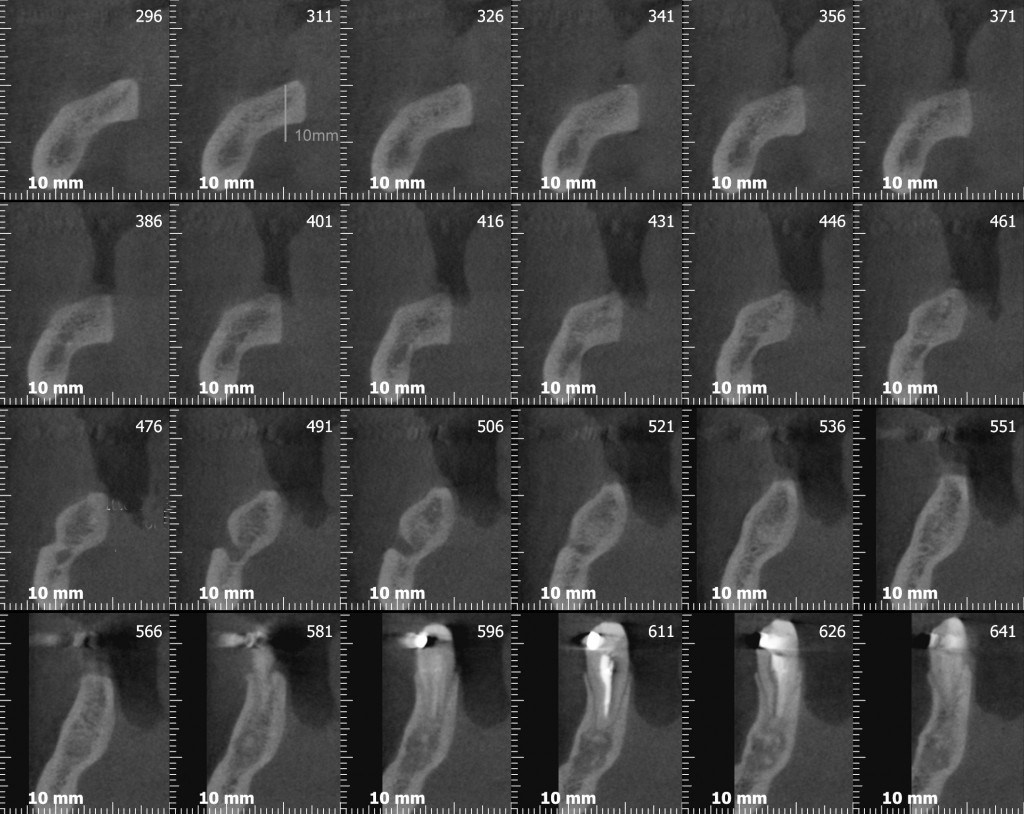

Adesso andiamo a vedere la cone-beam che sicuramente, secondo qualcuno, si sarebbe potuta evitare….

Se avessimo messo un impianto da 10mm nella zona del sesto con un asse protesicamente corretto avremmo proiettato tre o quattro millimetri delle nostre frese rotanti nella loggia sottomandibolare con tutti i danni potenziali che questi avrebbe potuto generare (se non l’hai ancora fatto vai poi a leggere l’articolo che ho linkato prima!).